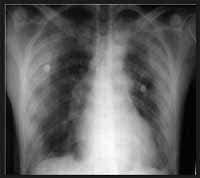

En la radiografía de tórax se evidencian infiltrados de ocupación alveolar y reticulonodular en ambos campos pulmonares de distribución periférica y áreas de vidrio esmerilado (Figuras 1A y 1B). Se realiza fibrobroncoscopia y lavado broncoalveolar (BAL).

| Figura 1A. Rx Tórax AP: Observe los infiltrados alveolares periféricos de predominio periférico (corteza pulmonar). | Figura 1B. Acercamiento de los infiltrados alveolares periféricos. |